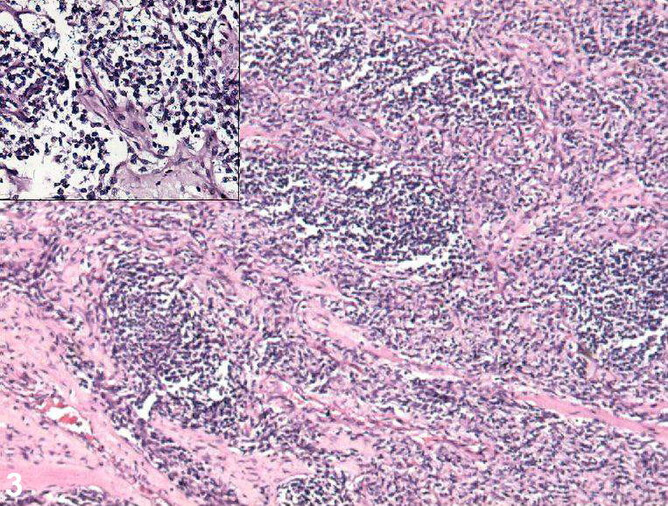

Rhabdomyosarcoma, or RMS, is an aggressive and highly malignant form of cancer that develops from skeletal (striated) muscle cells that have failed to fully differentiate. It is generally considered to be a disease of childhood, as the vast majority of cases occur in those below the age of 18. It is commonly described as one of the "small, round, blue cell tumours of childhood" due to its appearance on an H&E stain. Despite being a relatively rare cancer, it accounts for approximately 40% of all recorded soft tissue sarcomas.